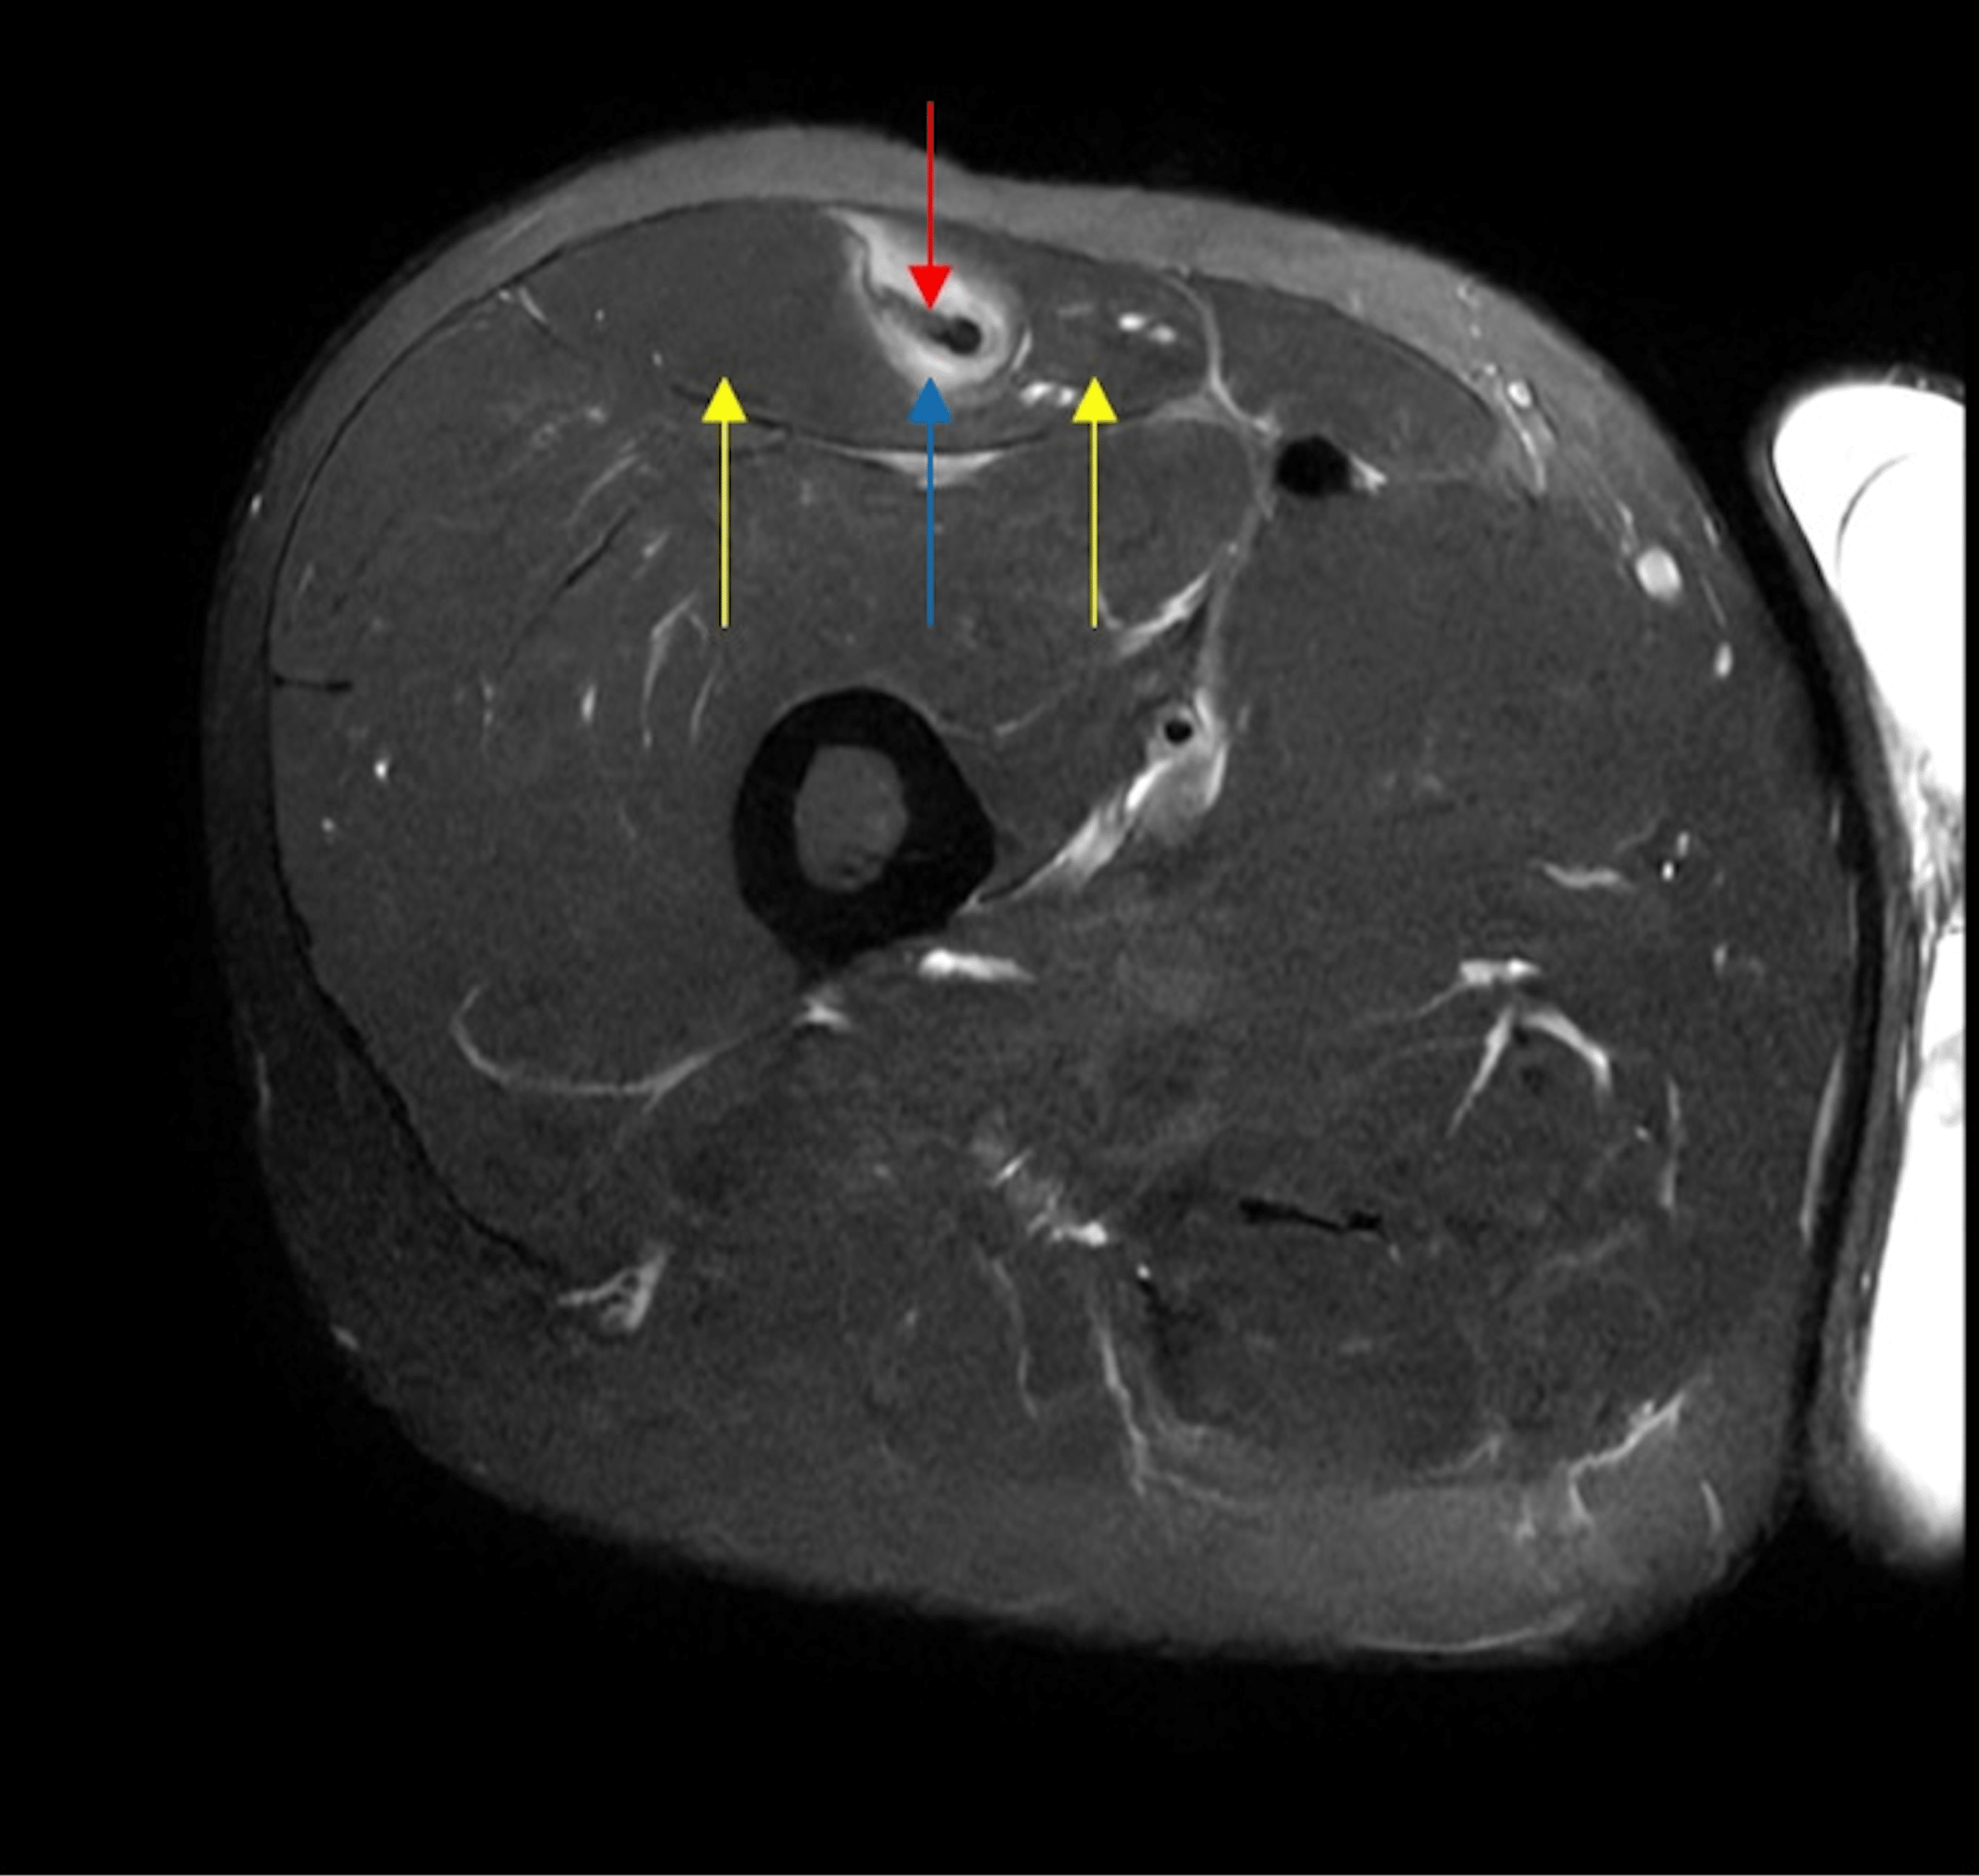

From www.cureus.com

Intramuscular Degloving Injury of the Rectus Femoris From Kickball A Kickball Knee Injury Sciatic pain that radiates down into the back of your leg, knee, and/or lower leg. 34.4% were sprains, strains, or muscle tears, while another 24.8% were. The current management of contusions includes ice, compression, elevation and the lengthening of the damaged muscle area. Warming up increases the temperature in your muscles, making them more pliable and less prone to strains,. Kickball Knee Injury.

Intramuscular Degloving Injury of the Rectus Femoris From Kickball A Kickball Knee Injury Warming up increases the temperature in your muscles, making them more pliable and less prone to strains, sprains, or. How to prevent, recognize & treat. Swelling within the knee joint is a symptom rather than a. Professional kicking coach brent grablachoff discusses the #3 most common kicking injury (quadriceps). These injuries should be treated equally as important as those such. Kickball Knee Injury.